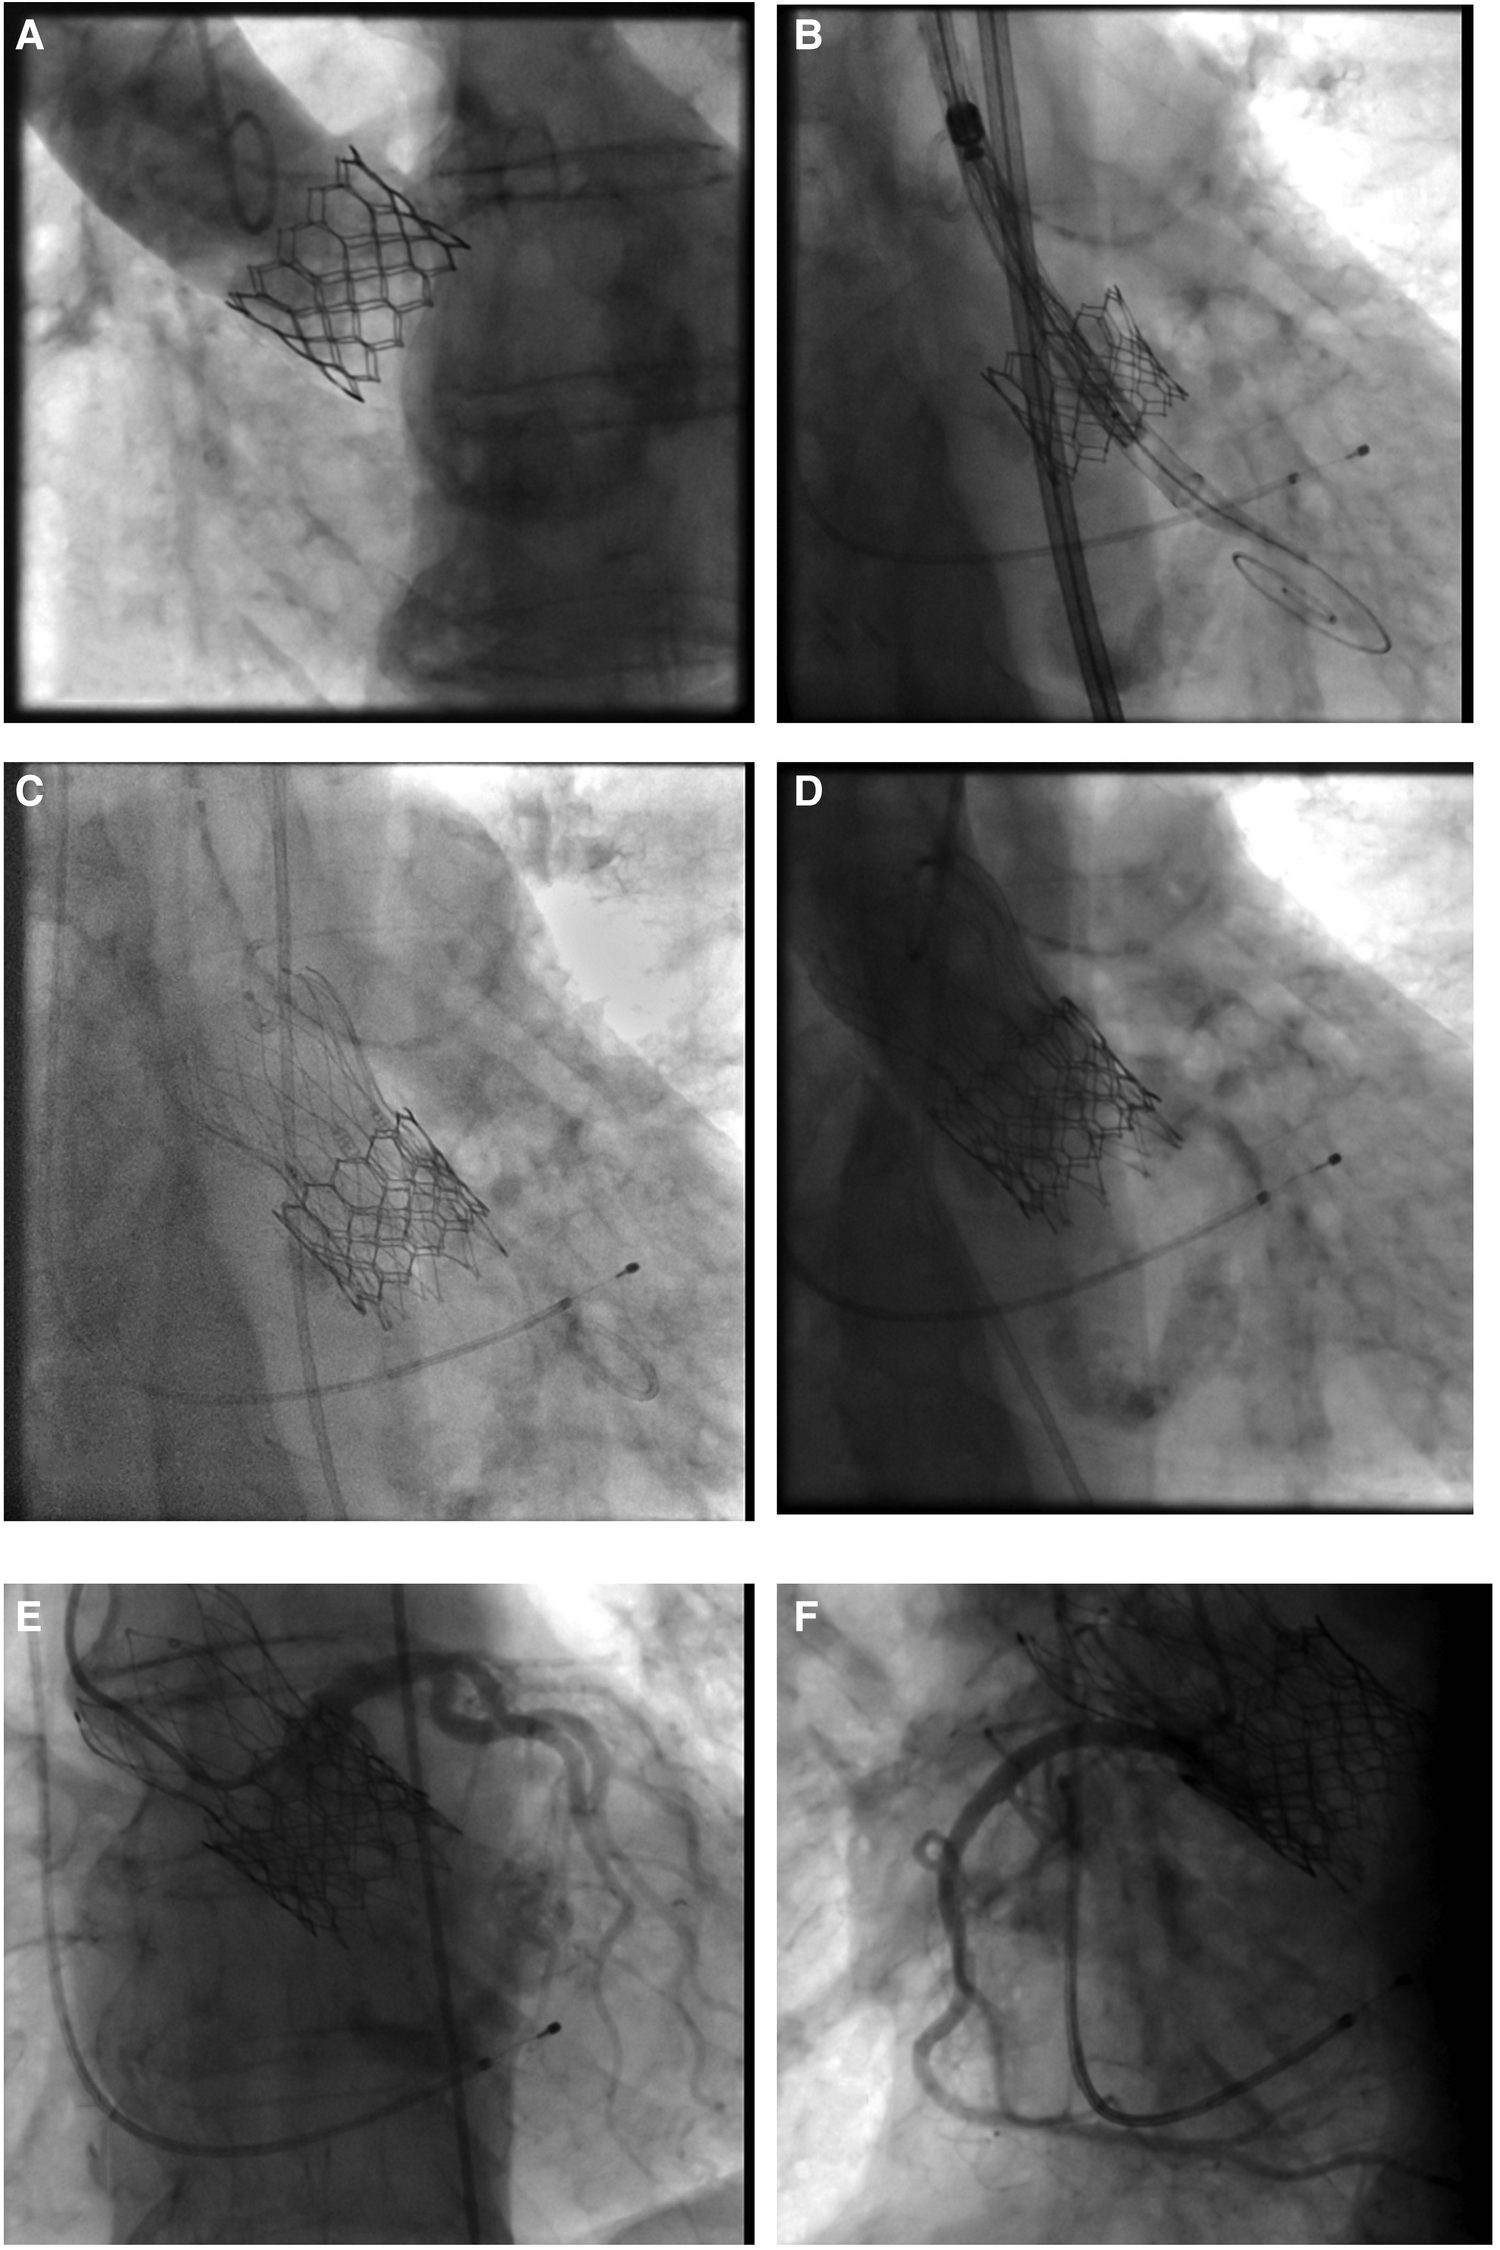

Figure 2

Valve-in-valve procedure using a self-expanding intra-annular transcatheter heart valve for treatment of a failing balloon-expandable transcatheter heart valve. (A) Failing balloon-expandable transcatheter heart valve in fluoroscopy with adequate distance of coronary arteries to the aortic annulus and marginal sinus width. (B) Placement of a 25 mm self-expanding intra-annular transcatheter heart valve into the Sapien 3, 26 mm (True ID: 21.5 mm) in deep position to protect against coronary occlusion. (C) Final position with (D) absence of paravalvular leakage. (E,F) Sufficient coronary perfusion in selective angiography of coronary arteries.